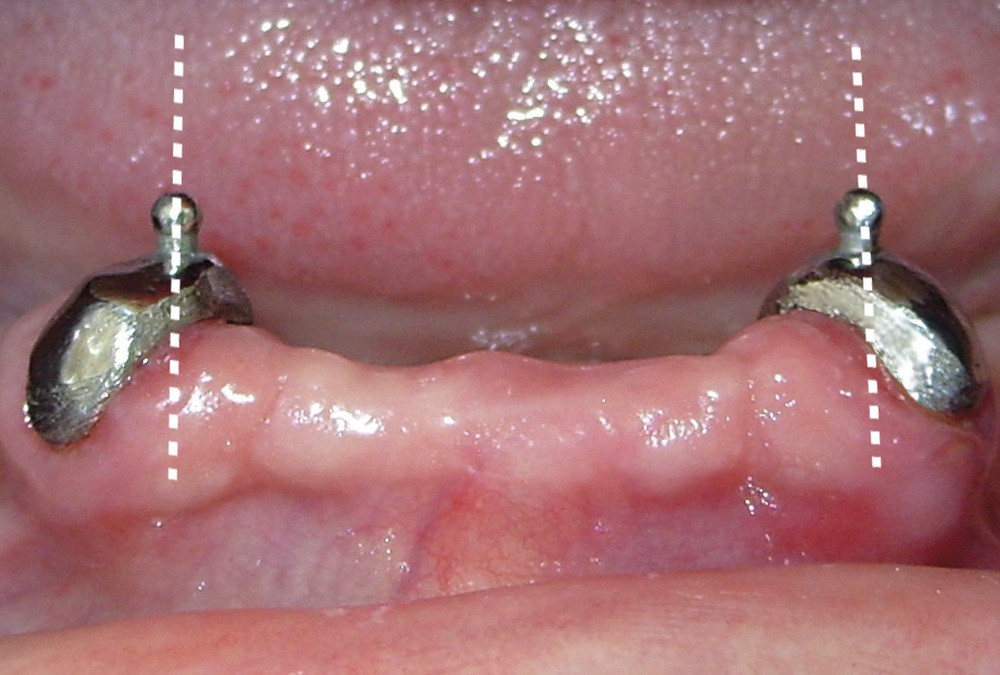

9. Parallélisme des axes radiculaires.